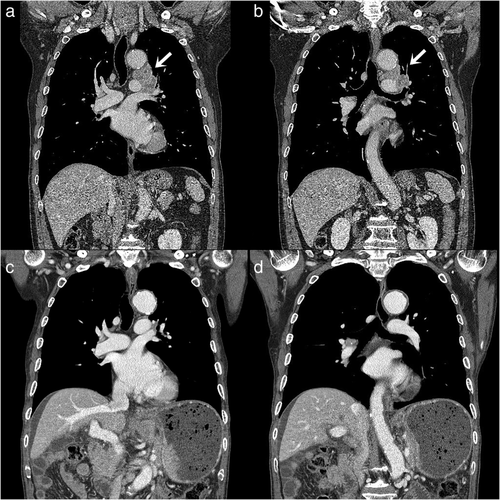

图2:(a和b)胸部CT示左上叶肿瘤,左肺门及纵隔淋巴结肿大;(c和d)胸部CT示既往肿瘤病变完全消失

“奇迹”出现了!胸部X线检查没有显示左肺门有轮廓突出的病变(图1b)。胸部CT扫描证实,先前左上叶、纵隔和肺门的SCLC完全缓解(图2c、d)